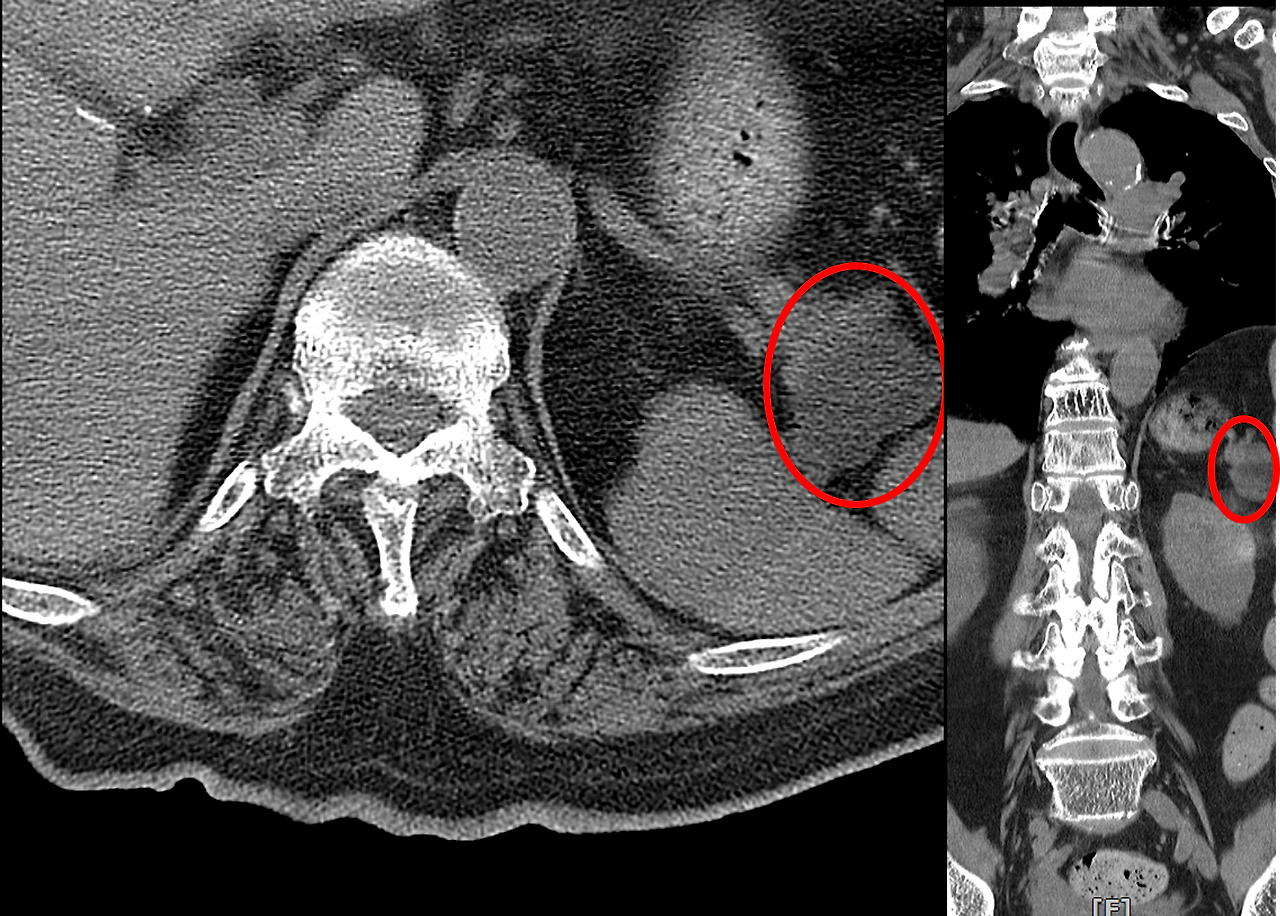

600장이 넘는 CT 사진을 하나하나 확인하던 중, 예상치 못한 소견이 눈에 들어왔다. 췌장 꼬리 부분에 약 3.5cm 크기의 혹이 보였다. 물혹일 가능성이 높아 보였지만, 이 크기라면 그냥 넘어갈 수는 없었다. 물혹일 가능성이 높지만, 그래도 모른다. 재내원하여 정밀 검사를 권했다.